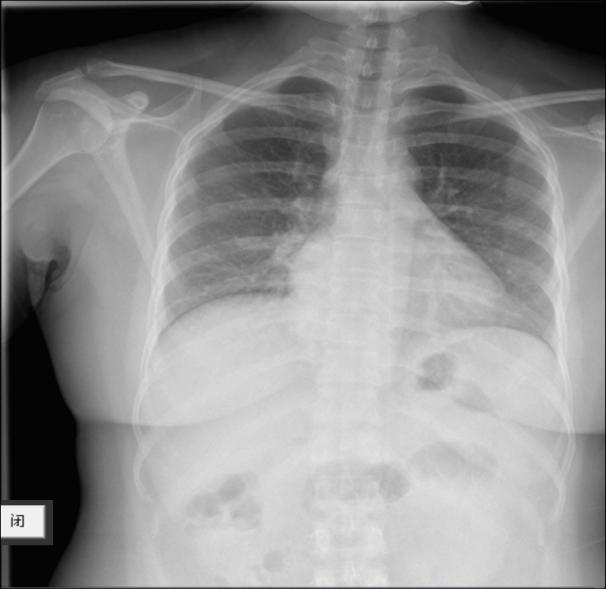

5天前查血常规+CRP:WBC 4.34×109/L,N 82.5%,L 0.52×109/L,CRP 1.9mg/L,考虑“上呼吸道感染”,予酚麻美敏、头孢拉定、左氧氟沙星等治疗,仍反复发热,并出现剧烈干咳。2天前复查血常规+CRP:WBC 3.98×109/L,N 70.6%,L 1.0×109/L,CRP 11.0mg/L。胸片:两肺纹理稍模糊(图1),为进一步诊治拟“感染性发热:病毒感染?”收住入院。

(图1 胸片检查)